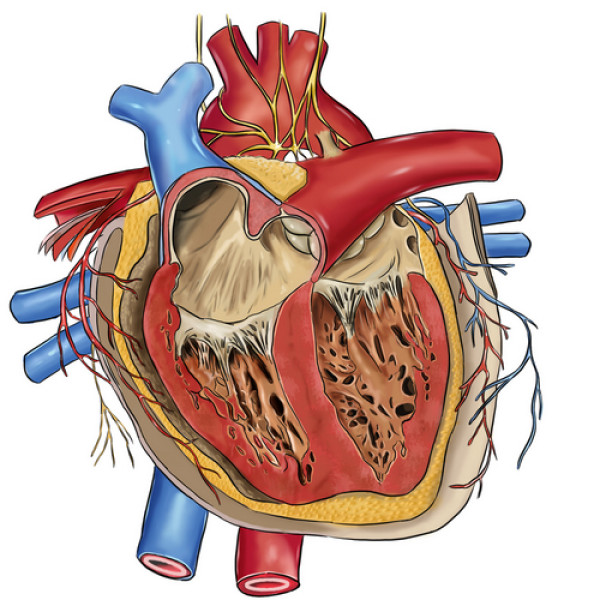

Фотографии и информация о приобретенных пороках сердца